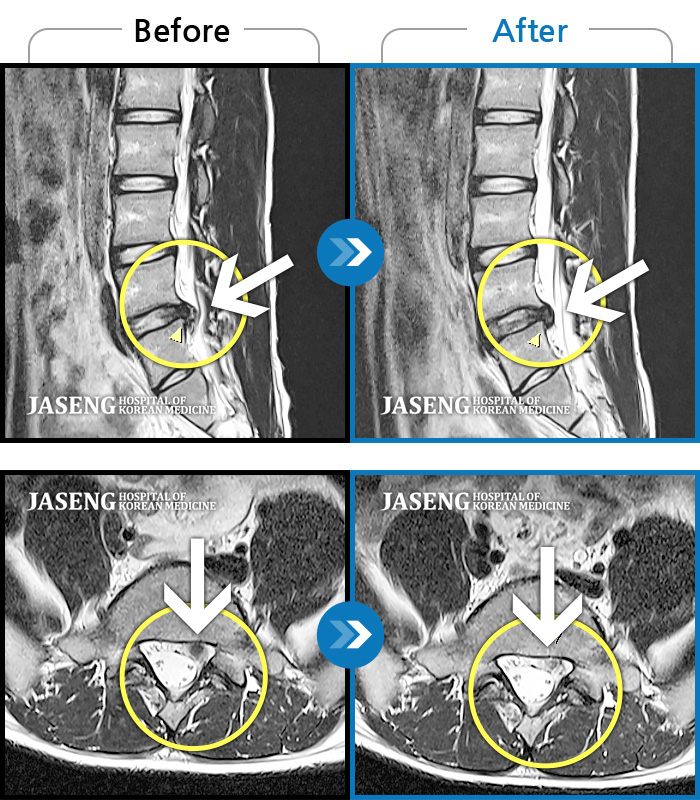

MRI 치료사례

좌측 허리부터 골반까지 통증, 골반이 틀어짐